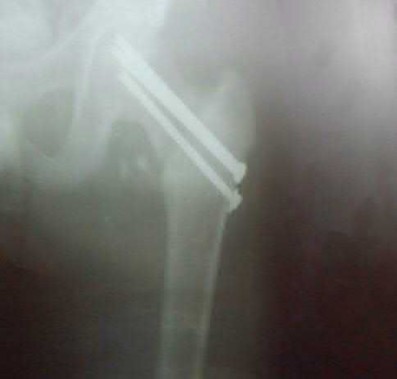

Question 1:

A 12-year-old obese boy presents with vague left thigh and knee pain. He is diagnosed with a Slipped Capital Femoral Epiphysis (SCFE) as seen in similar clinical scenarios. During percutaneous in-situ fixation, unrecognized penetration of the guide wire into the hip joint occurs. What is the most likely specific complication resulting from this technical error?

Correct Answer: Chondrolysis

Explanation:

Chondrolysis is a severe complication of SCFE characterized by rapid destruction of the articular cartilage. While it can occur idiopathically, its most established iatrogenic cause is unrecognized intra-articular hardware penetration. The 'approach-withdraw' fluoroscopic technique is required during pinning to assure pins are entirely intraosseous. Avascular necrosis (AVN) is usually due to damage to the epiphyseal blood supply (retinacular vessels) secondary to the initial displacement, forceful closed reduction, or posterosuperior pin placement.